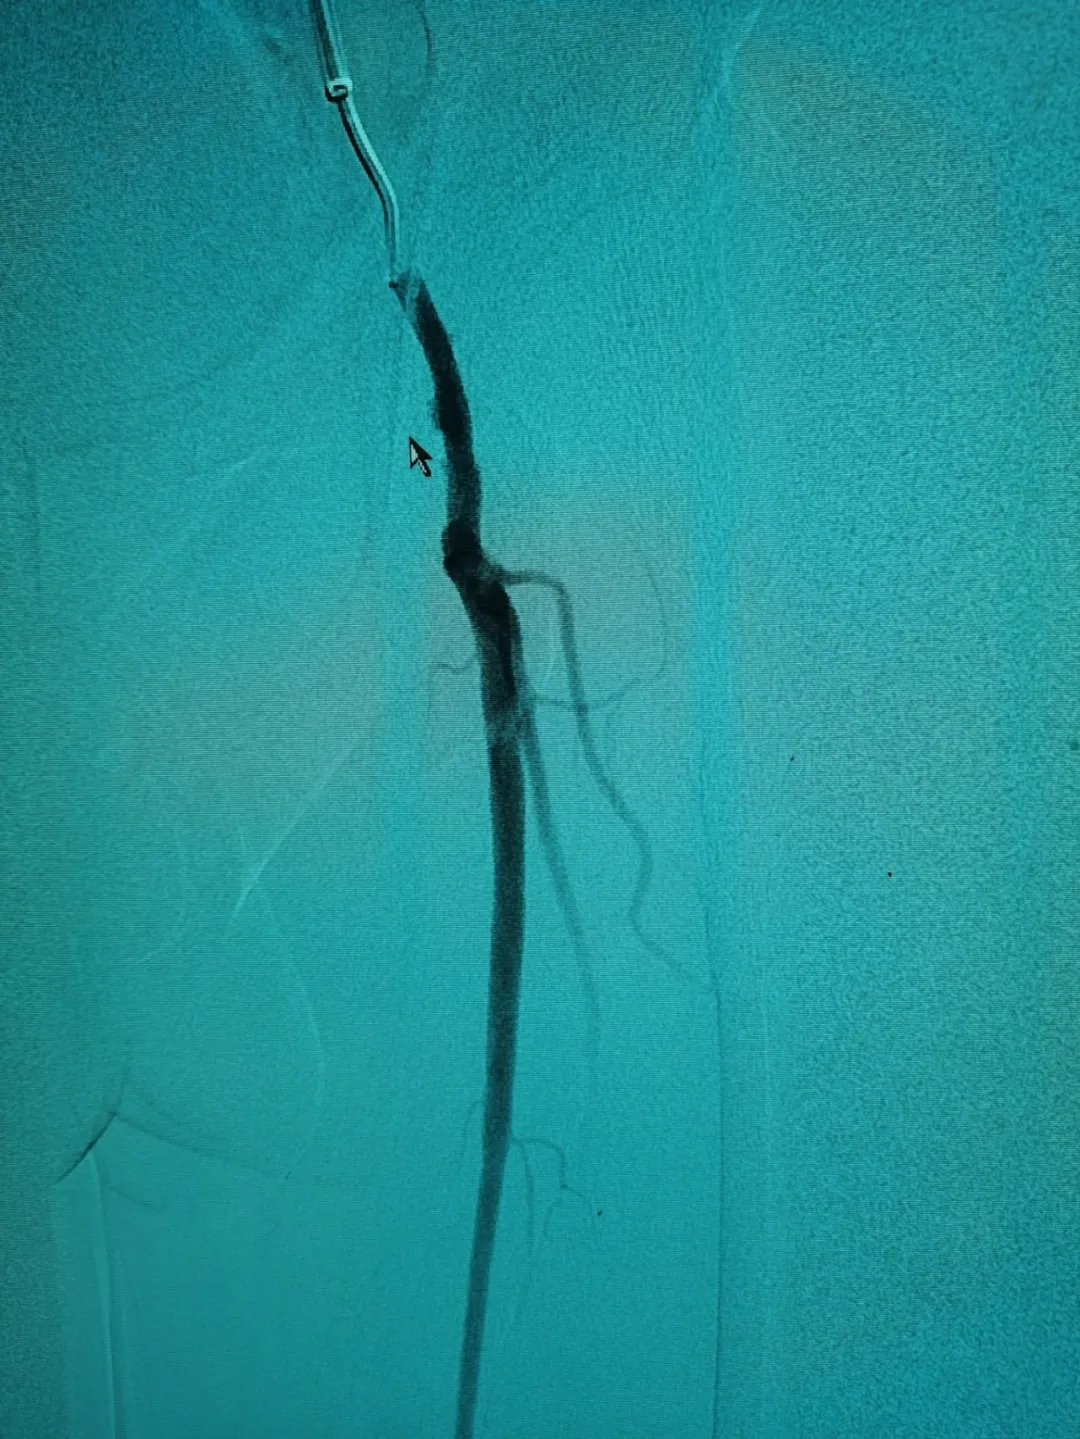

3月中旬,家人帶其到我院神經(jīng)外科治療。“根據(jù)患者的描述,是非常典型的間歇性跛行,我們給他做了雙下肢的血管造影,進一步證實了這一點。”施宏飛主任說,通過影像學(xué)檢查發(fā)現(xiàn),患者血管存在嚴(yán)重鈣化的斑塊,且左側(cè)股總動脈下段中重度狹窄,左側(cè)股淺動脈下段重度狹窄。

經(jīng)過周密的術(shù)前討論,施宏飛主任在團隊專家王明義副主任醫(yī)師及介入手術(shù)室醫(yī)護人員的配合下為患者實施了左側(cè)下肢動脈斑塊旋切+藥物球囊擴張術(shù)。

將這些動脈斑塊清除之后,又利用球囊為患者進行血管擴張,病變血管形態(tài)改善良好,可以清楚看到血管內(nèi)大量增生內(nèi)膜被旋切出來,取出遠端保護傘可以看見大量過濾的內(nèi)膜組織。